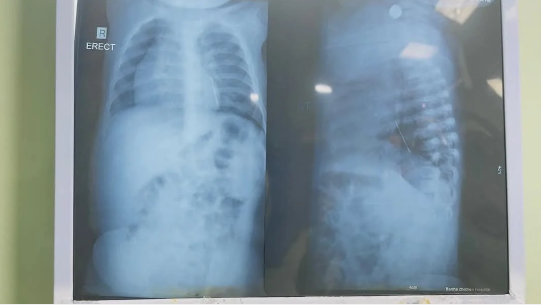

نجح فريق جراحي بمستشفى الأطفال التخصصي ببنها بمحافظة القليوبية، في استخراج "دبوس طرحة"، من صدر طفلة كانت تعانى من كحة مستمرة وعدم القدرة على التنفس، وذلك بعد حجزها بالمستشفى وإجراء الإشاعات والفحوصات الطبية اللازمة.

وكشفت إدارة مستشفى الأطفال التخصصي ببنها، في بيان لها، أنه نجح فريق جراحي بالمستشفى، في استخراج دبوس طرحة من صدر طفلة كانت تعاني من كحة مستمرة، وعدم القدرة على التنفس، وبحجزها بالمستشفى وإجراء الإشاعات والفحوصات الطبية اللازمة، تبين وجود دبوس طرحة على الصدر.

وتابعت مستشفى الأطفال التخصصي ببنها، أنه تم على الفور دخول الطفلة غرفة العمليات، واستطاع الفريق الطبى برئاسة الدكتور محمد محمد متولى استشاري جراحة الأطفال، والدكتور عمرو عبد الملك أخصائي الجراحة، وفريق التخدير، من استخراج الدبوس وخرجت الطفلة على العناية المركزة، وتم شفاء الحالة وخروجها من مستشفى الأطفال التخصصي ببنها.